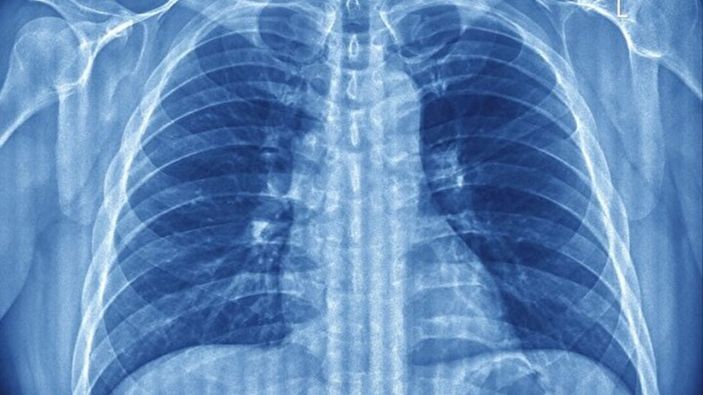

ABD merkezli bir araştırma ekibi, derin nefes almanın akciğerlerin çökmesini engelleyen ve alveol adı verilen hava keseciklerini koruyan doğal bir mekanizma olduğunu ortaya koydu.

Science Advances dergisinde yayımlanan çalışmada, fareler üzerinde yapılan deneylerde iç çekmenin akciğerlerdeki yüzey gerilimini azaltan bir maddeyi yeniden aktif hale getirdiği gözlemlendi.

Bu madde, her nefes alışta hava keseciklerinin çökmesini engelleyerek oksijen alışverişini sürdürülebilir kılıyor.

Araştırmacılara göre bu refleksin temel amacı, akciğer yüzeyinin kurumasını ve yapışmasını önlemek.